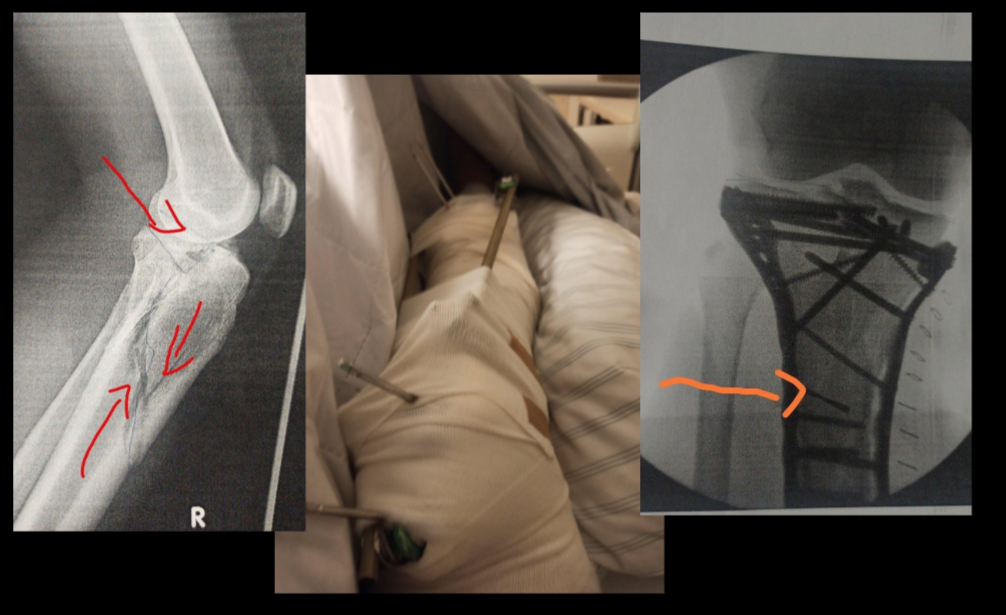

3D Visualization for Surgical Planning

MRI Scanner

CT Scanner